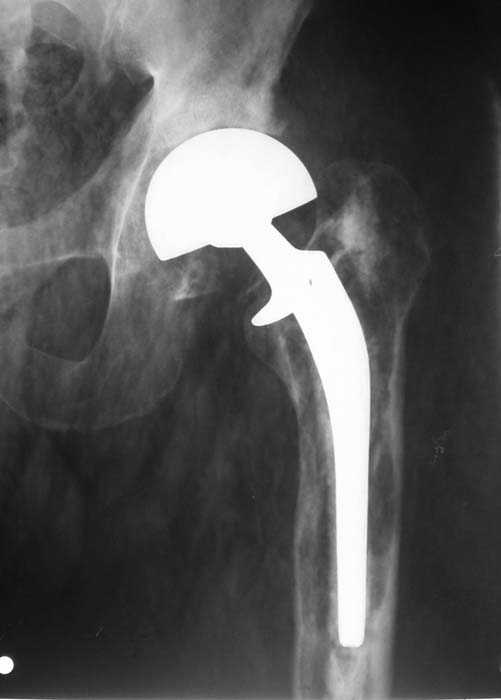

Мужчина, 39 лет.По поводу двустороннего асептического некроза головок бедренных костей последовательно выполнено тотальное эндопроезирование левого (1998 г), затем правого (1999 г) тазобедренных суставов.

22/10/04

Нет никакого смысла делать операцию в два этапа. С чашкой все понятно - стандартный подход с установкой пресс-фит компонента. На бедре имеет

место перипротезный перелом В3 типа - т.е. перелом вокруг ножки с ее нестабильностью на фоне выраженного остеолиза. Решение - доступ к каналу

через перелом с удалением самой ножки, костного цемента и рубцовых тканей. Установка ножки дистальной фиксации (типа Solution), длину ножки

надо определить по шаблону. Минимальный контакт ножки с интактной костью - 6-8 см. Фрагменты проксмального отдела собираются на ножке

эндопротеза, дефекты костной ткани заполняются чипсами (аллографт) и фиксируются кортикальными аллографтами, уложенными дополнительно по типу

"вязанки хвороста" серкляжом. Мы имеем 8 или 10 подобных наблюдений и результатами довольны.